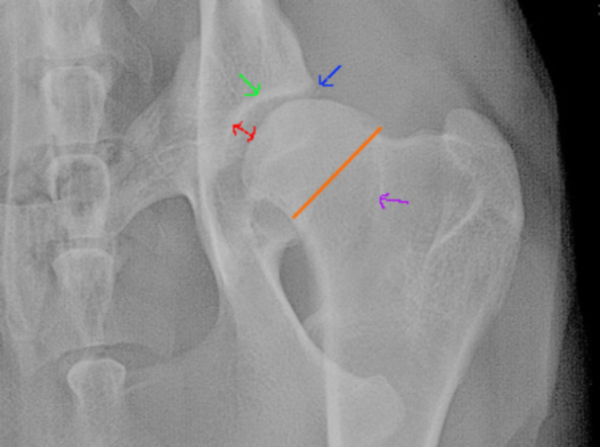

Dan de aansluiting en de botafwijkingen. Even de linkerheup (denk ik) gepakt:

Rode streepje: de afstand tussen de heupkop en de heupkom: veel wijder dan zou moeten, onvoldoende of slechte aansluiting dus.

Groene pijltje: de heupkom is instabiel en het lichaam probeert dat op te vangen door meer mineralen af te zetten op het bot (sterker maken dus). dat heet sclerose en zie je dus als een wittere streep.

Blauwe pijltje: aan de rand van de heupkom wordt extra bot aangemaakt om het gewricht te stabiliseren.

Orange streep: de nek van de femur is dikker dan normaal

Paarse pijltje: Om de extra spanningen in het bot (die ontstaan door de instabiliteit) op te vangen wordt meer mineraal afgezet, dit heet een Morgan-lijn.

Ik ben trouwens minder streng dan Inge O en dit zou voor mij een D heup zijn, of zelfs C, afhankelijk van het ras, de leeftijd en de activiteit van de hond. Als dit een Duitse herder of een Molosser van 7 jaar oud zou zijn, die zijn hele leven actief gesport heeft, zou het een C zijn. Is het een tweejarige Mechelse herder zonder extreme activiteit, dan D. Is dit een DH en stuur je de foto's ter beoordeling naar Duitsland dan maak je nog een goede kans op een B, schat ik zo in.